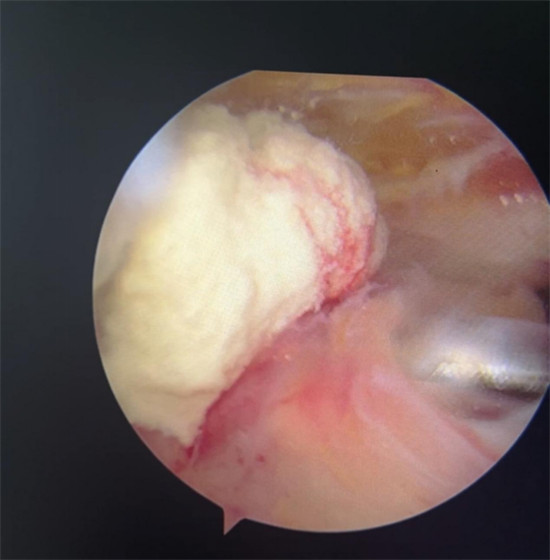

賀大媽慕名來廣安醫(yī)院找羅軍主任就診,面對羅醫(yī)生,賀大媽哭訴:“羅醫(yī)生,我真想剁下自己的這只胳膊。”羅軍主任根據(jù)患者的癥狀拍片,診斷為岡上肌鈣化性肌腱炎,隨后,羅醫(yī)生為李大媽進行了肩關(guān)節(jié)鏡微創(chuàng)手術(shù),竟從她的右肩“擠”出“牙膏”。

鈣化性肌腱炎是一種自限性疾病,就是疾病發(fā)生發(fā)展到一定程度后,經(jīng)長期機體調(diào)節(jié)能夠控制病情發(fā)展并逐漸恢復(fù)痊愈。它分為四個階段:鈣化前期、鈣化形成期、鈣化吸收期、鈣化后期,往往在“鈣鹽斑塊”吸收時,疼痛最劇烈,賀大媽就正處于“吸收期”。

羅軍主任表示,很多人會把肩痛都歸因于肩周炎,這是一個很大的誤區(qū)。其實,肩痛人群中只有15%左右是肩周炎,大部分肩膀疼痛由于肩袖損傷、肩峰撞擊征、鈣化性肌腱炎。而大多數(shù)人也因此認(rèn)為忍一忍就會自愈,常常延誤治療,關(guān)節(jié)鏡微創(chuàng)治療鈣化性肌腱炎,可以快速緩解疼痛,同時可以修復(fù)肩袖損傷,清理肩膀骨刺。